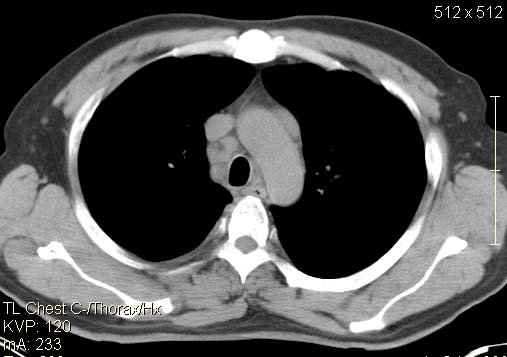

以下是引用qc80012345在2007-4-17 12:33:00的发言:[br]右肺下叶周围型肺癌伴肺门及纵隔内淋巴结转移;比较清楚。

以下是引用qingyuan在2007-4-17 14:19:00的发言:[br]右肺下叶外侧后段胸膜下区节结样病变、分叶、内可见空洞,壁厚薄不均,胸膜凹陷、肺门周围区纹理增粗、僵硬、并近似小结节样改变,肺门区软组织节结、纵膈淋巴结肿大,患者病史长、抗炎治疗无好转炎性改变基本排除,考虑:右肺下叶周围型肺癌伴纵膈及右肺门区淋巴结转移、肺内淋巴管受侵。